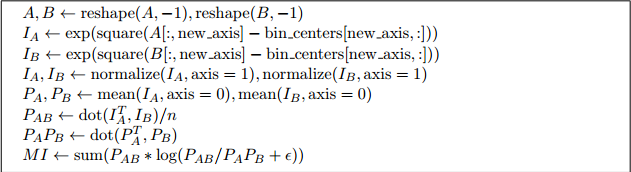

3.2 Vectorized MI

要在VoxelMorph中使用global和local MI,必须以向量化vectorized的方式实现它们。向量化vectorized操作比循环操作运行速度快得多,而且由于每次通过网络的一对图像都必须计算MI损失,我们只能使用向量化操作来实现MI,否则体素形态将不能及时训练。

3.2.1 Vectorized Global MI

为了计算两幅图像A和B的global MI,我们首先计算矩阵和

,每个都有shape num_voxels×num_bins,表示每个体素对每个强度bin的贡献,如式(3.2)所示.这可以通过首先对图像进行重塑reshaping和tiling平铺,使其具有num_voxels×num_bin维数,减去bin中心的强度,然后进行element-wise操作来计算高斯函数。然后沿着0轴计算分布

和

和 ,以及沿着0轴计算

,以及沿着0轴计算和

的均值。计算联合分布

,我们简化

,我们简化 ,其中n是每张图像中的体素数,因为这将准确地给我们公式(3.3)中的总和。

,其中n是每张图像中的体素数,因为这将准确地给我们公式(3.3)中的总和。

算法1、global MI 的伪代码